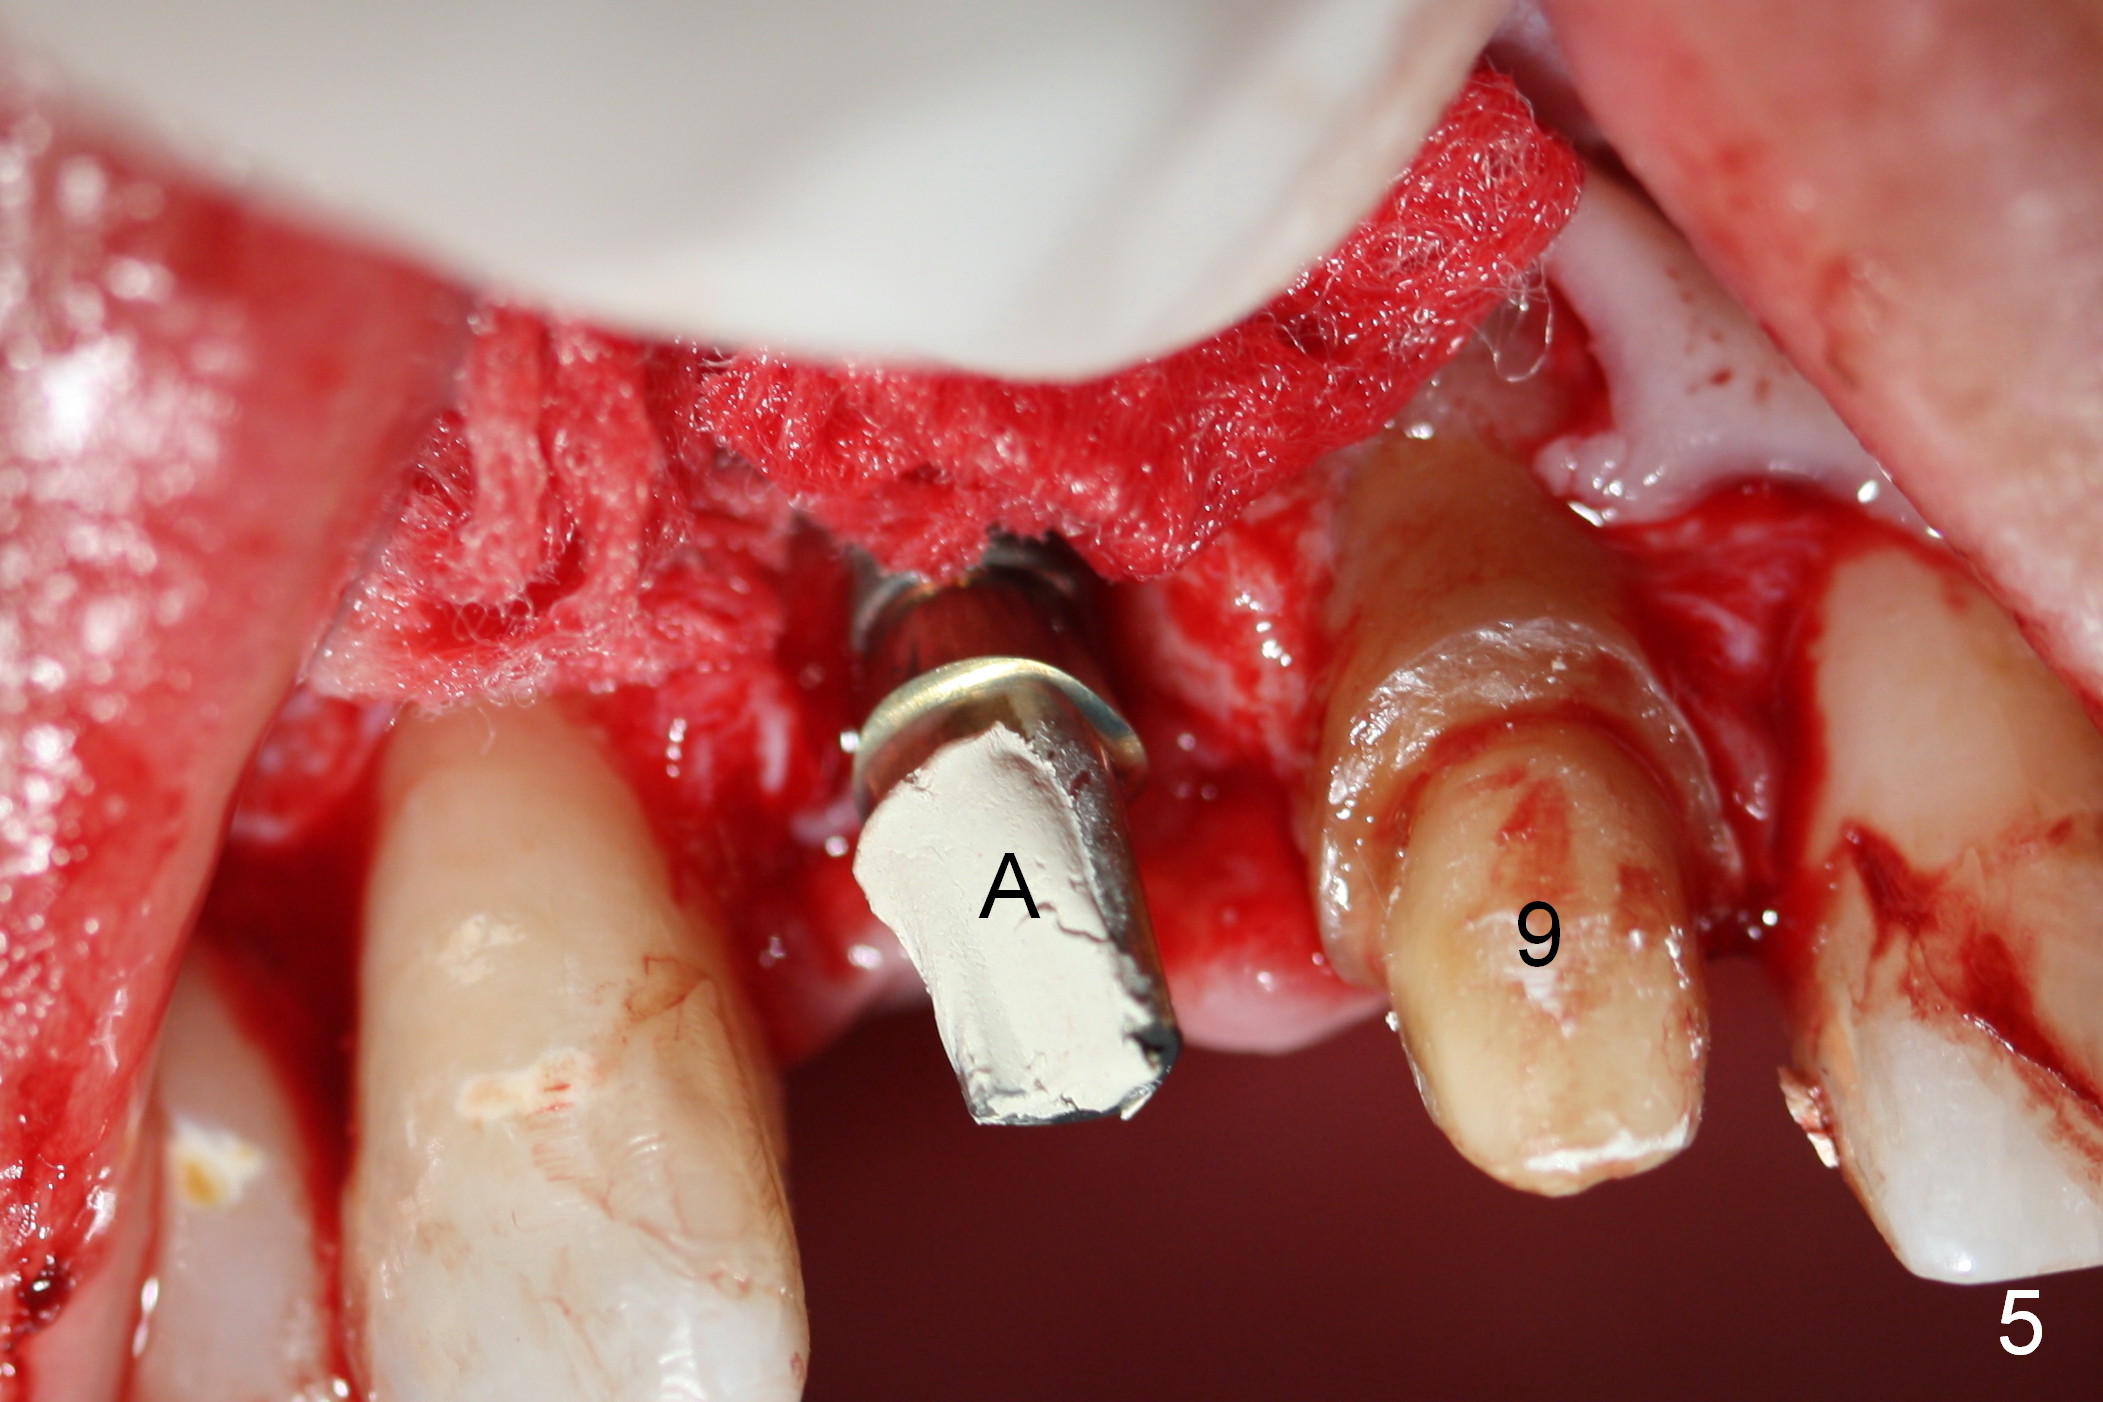

The patient returns for Zirconium abutment retrieval 1 month post its fracture.  When the provisional is removed, the gingival pontic morphology remains (Fig.2).  There is no problem to remove the abutment screw (Fig.1 with its driver), whereas it is difficult to remove the remaining abutment (Fig.2 *) due to limited access.  When the access improves by incision (Fig.3), buccal implant thread exposure is confirmed and the fractured abutment (*) is to be removed easily.  A 15° angled abutment (A) corrects the angulation, but not the position (Fig.4,5, compare to Fig.1 with a driver in place).  After being trimmed, the labial contour of the abutment is equivalent to that of #9 (Fig.6,7), but the margin is higher.  Using an abutment with taller gingival height (from 2 mm to 3 mm) may alleviate the margin issue.